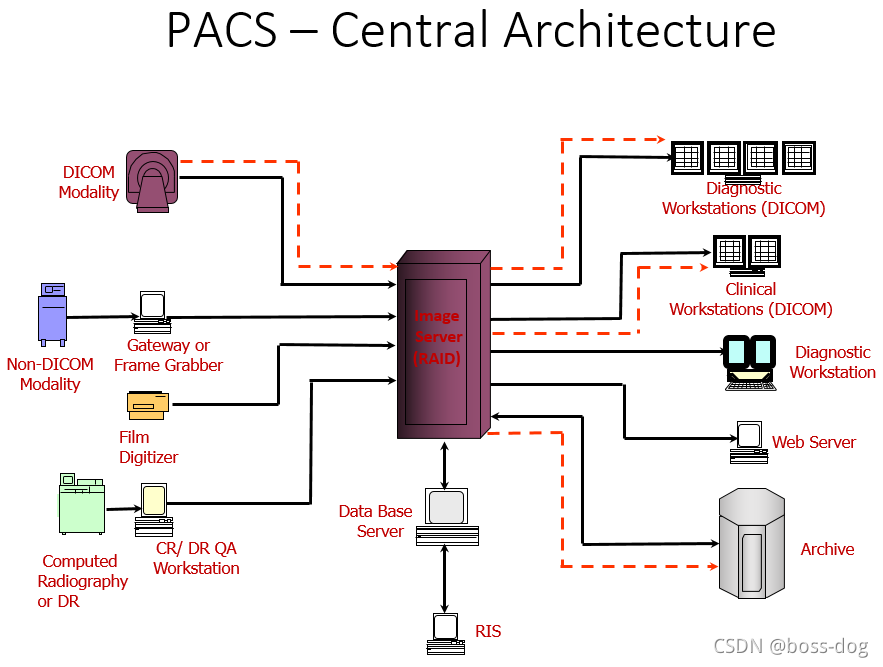

PACS分为两种:一种是图像的服务器为中心(PACS – Central Architecture),还有一种是分布式的(PACS – Distributed Architecture)。

PACS – Central Architecture的优缺点:

优点:传输起来的统一管理,并且所有的数据都在服务器里面方便管理。

缺点:服务器的功能需要非常强大,以满足不停的接收和分发那些图片和信息,需要很高的性能;而且如果服务器坏了,导致整个系统瘫痪;对带宽也有一定的要求。

- PACS系统的组成:

HIS/ RIS(关于病人的信息、预约信息)

Broker(代理)

ePR gateway(网关)

Database Server(数据库)

Image Server (RAID)(图像数据库)

Long Term/ Near line Archive(长期、近期的档案整理)

Networks(网络)

Digitizer(数字化处理)

Acquisition Gateways(采集网关)

Non-DICOM modality gateway(非DICOM格式图像的处理)

DICOM Print Server(需要连接胶片打印机)

Media Server(拷刻成光盘)

Reporting Server(形成意见报告)

Monitor QC Server(和显示器的连接)

Web Server(Web服务端)

Workstations(给医生看图片的工作站)